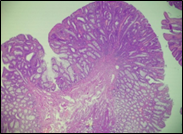

The present study concluded that, out of the total 77 patients with colorectal neoplasia, 17 (22.1%) had a high degree of differentiation (G1), 51 (66.2%) had a moderate degree of differentiation (G2), and 9 (11.7%) had a low degree of differentiation (G3). Figure 3 illustrates the different morphopathological forms of colorectal neoplasia observed in the patients included in the study.

A | B |

C | |

Fig. 3 Morphopathological forms of colorectal tumors (degree of differentiation) A – conventional highly differentiated colonic adenocarcinoma (G1) (HE stain, ×200) B – moderately differentiated (G2) conventional colonic adenocarcinoma (HE stain, ×200) C – conventional poorly differentiated colonic adenocarcinoma (G3) (HE stain, ×200) | |

For patients with colorectal neoplasm, investigating the correlation between the macroscopic aspect of the tumor formation visualized endoscopically and the degree of differentiation described histologically, it was found that there is no statistically significant relationship (p > 0.05), which is above the threshold accepted for demonstrating a significant statistical correlation. It is known that most colorectal adenocarcinomas develop at the site of precursor lesions, such as adenomas and dysplasia. Residual adenoma is a phenomenon commonly found in colorectal adenocarcinomas. Typical adenomas are subclassified into tubular, tubulovillous, and villous types based on their architectural and histological features. Tubular adenomas consist of dysplastic glands that resemble cryptic intestinal glands and contain less than 25% villous component. Villous adenomas are composed of more than 75% villous components, which appear as fibrovascular rods covered by dysplastic epithelium. Tubulovillous adenomas represent intermediate lesions with a villous component ranging from 25% to 75%.